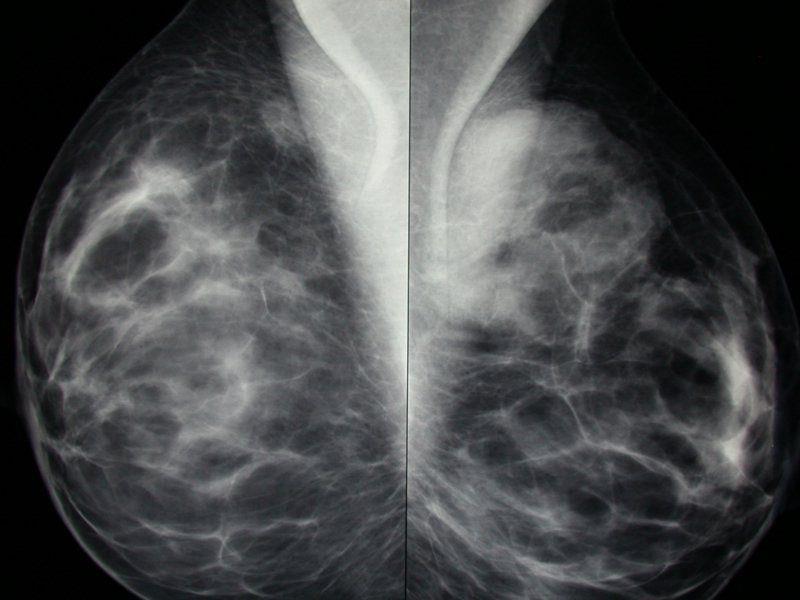

בתמונה: דוגמא לממוגרפיה תקינה - לכל שד מבצעים שני צילומים: אלכסוניים (הצילומים העליונים) ואנכיים (הצילומים התחתונים)